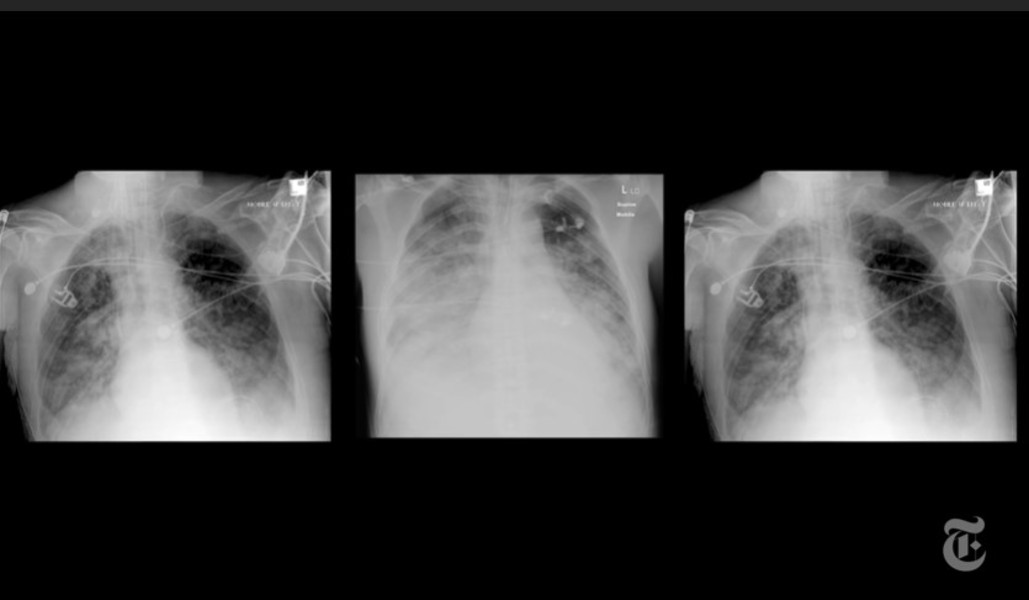

Medicii de la Spitalul Clinic Judeţean de Urgenţă Arad atrag atenţia că, în ultimele trei săptămâni, au remarcat gravitatea leziunilor pulmonare la pacienţii tineri infectaţi cu virusul SARS-CoV-2, care s-au prezentat târziu la spital, necesitând de urgenţă Terapie intensivă, potrivit News.

Medicii de la SCJU Arad afirmă, într-o postare pe Facebook, că lezinile pulmonare grave care rămân în urma virusului „sunt de multe ori necruţătoare”, chiar dacă pacienţii ajung să se vindece de infecţie.

„Avem pacienţi internaţi în terapie intensivă COVID-19, nevaccinaţi şi cu afectare pulmonară semnificativă care – după ce testele COVID-19 devin negative – ajung pe secţia de Anestezie şi Terapie Intensivă I – non-COVID, pentru că sunt în continuare în stare gravă! Din păcate ne confruntăm cu situaţii în care plămânii sunt afectaţi în proporţie de 100%, iar viaţa pacientului nu mai poate fi salvată. Zilele trecute am avut un tânăr, de 24 de ani, care a stat acasă două săptămâni şi a dezvoltat o astfel de complicaţie, pe respiraţie spontană, necesitând imediat ventilaţie şi intubaţie mecanică, însă lupta cu virusul nu a mai putut fi câştigată”, arată dr. Cristian Nicolescu, medic şef Secţie Anestezie şi Terapie Intensivă I.